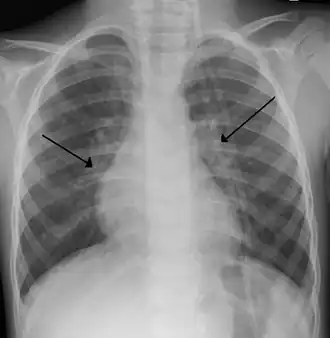

- La radiographie pulmonaire montre une opacité diffuse de la trame pulmonaire, une augmentation de la taille des espaces intercostaux et un abaissement des coupoles diaphragmatiques.